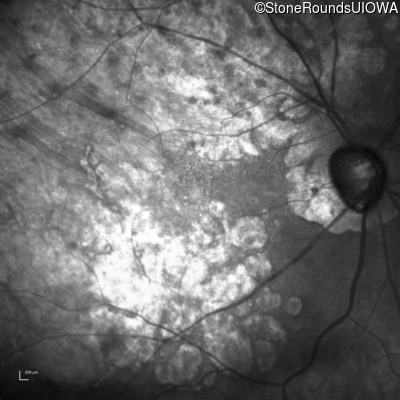

Infrared Fundus Photograph - Right - 20/25 -1

Exemplar